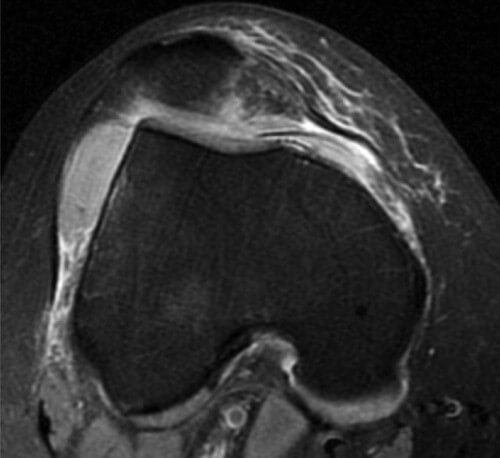

Fig. 1. CAPSULA ARTICULARA

Sectiune transversal IRM FSE PD.